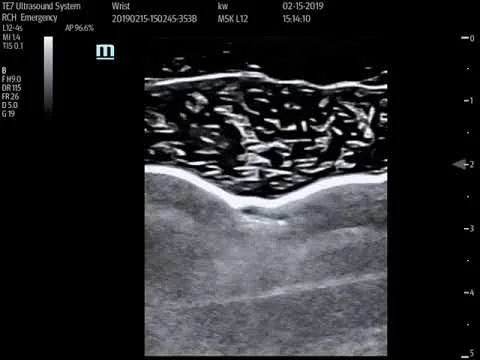

Distal radius fracture